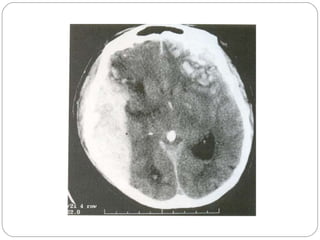

Cerebral or Extracerebral mass   Tumor Massive infraction with edema Contusion Parenchymal SDH : EDH Abscess

Cerebral or Extracerebralmass Tumor Massive infraction with edema Contusion Parenchymal SDH : EDH Abscess

Investigations CT Scan with Contrast  MRI with Contrast Except cerebral abscess  Technetium brain scan – destructive skull vault, skull base lesions EEG – Cerebral abscess, focal slow waves seen Skull Film- not useful in hemispherical tumors Routine tests  Angiography, volumetric MRI Lumbarpuncture only after imaging  Biopsy

Investigations CT Scanwith Contrast MRI with Contrast Except cerebral abscess Technetium brain scan – destructive skull vault, skull base lesions EEG – Cerebral abscess, focal slow waves seen Skull Film- not useful in hemispherical tumors Routine tests Angiography, volumetric MRI Lumbarpuncture only after imaging Biopsy